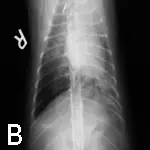

Right lateral (A) and dorsoventral (B) thoracic radiographs were taken. Notice the enlarged pulmonary artery (C, arrow) in the dorsoventral view, which provided a clue to her diagnosis.